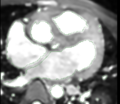

- Carma reg CT.jpg 923 × 923; 170 KB

- Carma registration screenshot.jpg 595 × 570; 210 KB